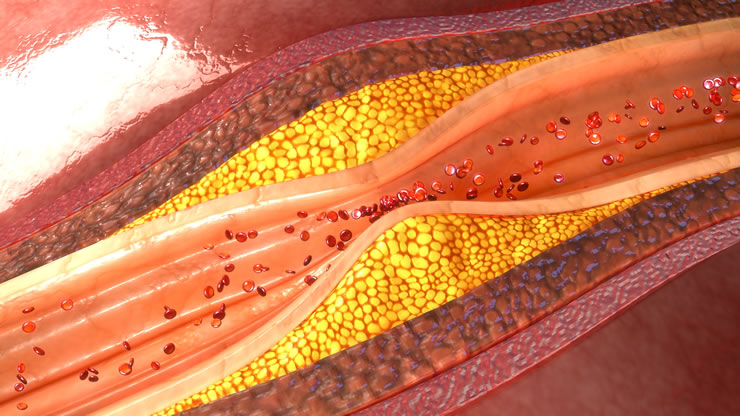

Η στεφανιαία νόσος είναι μια κοινή καρδιακή πάθηση στην οποία τα αιμοφόρα αγγεία που παρέχουν οξυγόνο και θρεπτικά συστατικά στον καρδιακό μυ στενεύουν ή αποφράσσονται από τη συσσώρευση πλάκας. Αυτό μπορεί να οδηγήσει σε μειωμένη ροή αίματος στην καρδιά, προκαλώντας πόνο στο στήθος (στηθάγχη) ή εμφράγματα μυοκαρδίου.